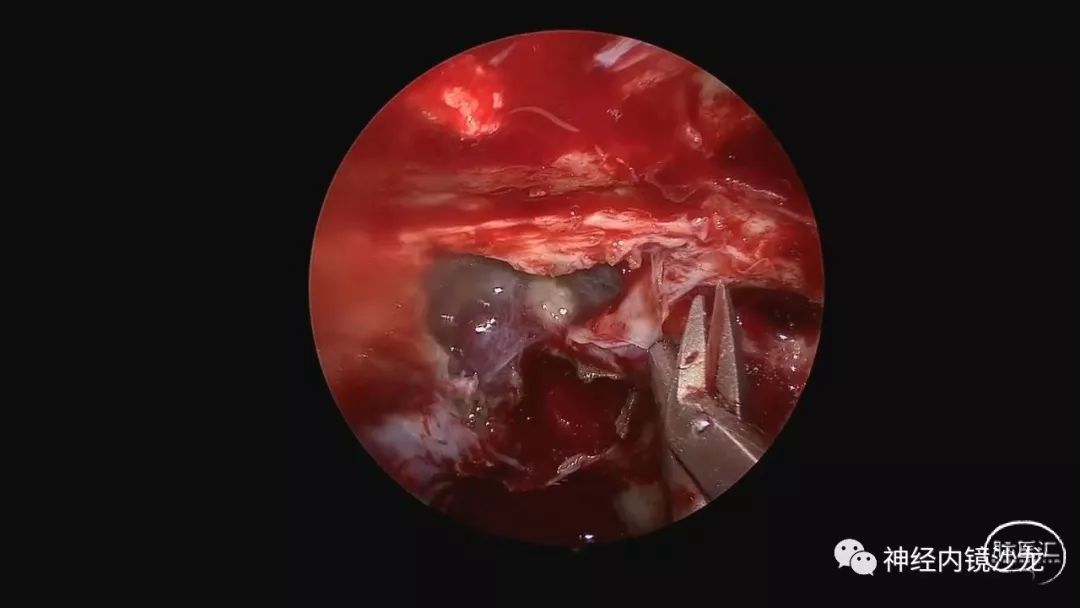

精彩图表

从事神经外科十余年,擅长神经外科肿瘤诊治,尤其是神经内镜微创手术治疗垂体瘤、颅咽管瘤、脑膜瘤等颅底肿瘤